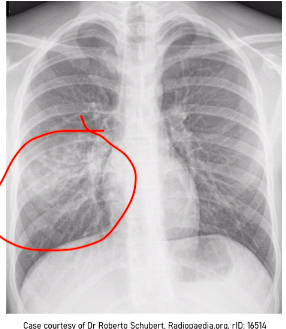

whats wrong here?

whitening of the lung - in the right middle zone of the lung